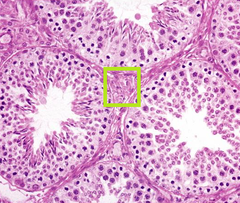

Normal seminiferous tubules Spermatogonia (near basal lamina) Spermatids (thin near lumen) Leydig cells

Front

What is this? Name the three main cells that you can see

Leydig cells (interstitial cells)

whats in the box